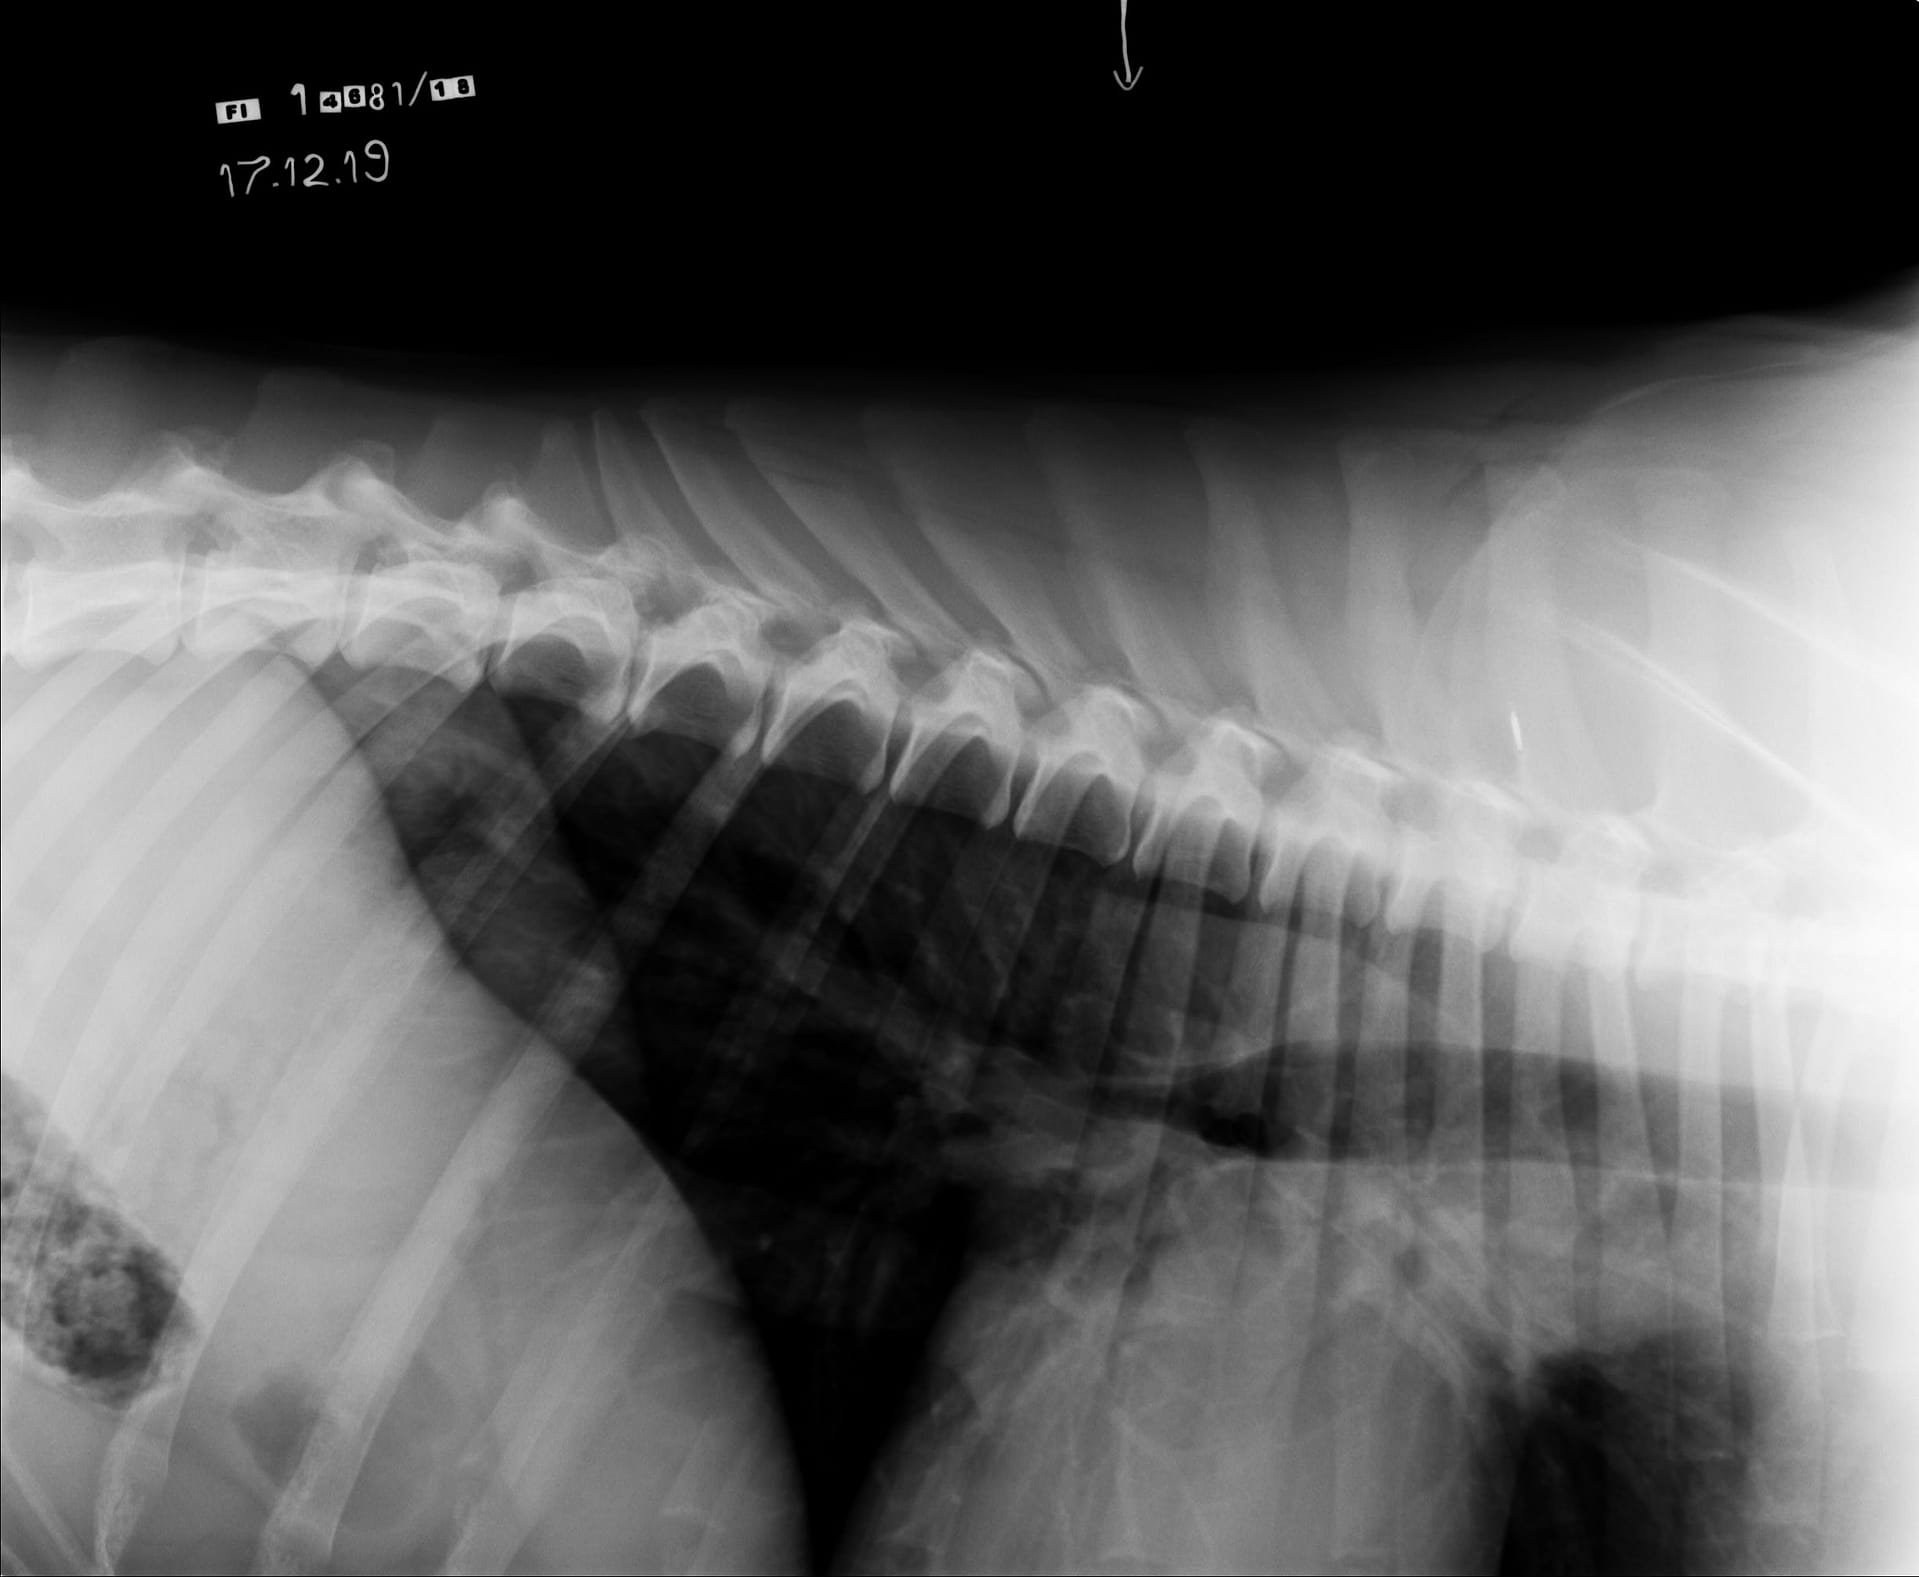

Tähän mennessä Iivo on ollut täysin terve ja Iivo tutkittiin luustoltaan terveeksi joulukuussa 2019. Luonnekuvaukseen (MH, laukausvarma) Iivo osallistui elokuussa 2020.

| Selkä: | LTV0, SP0, VA0 |